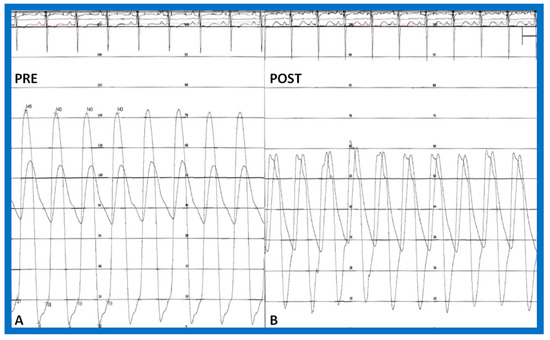

- Rao, P.S.; Solymar, L. Electrocardiographic changes following balloon dilatation of valvar pulmonic stenosis. J. Interv. Cardiol. 1988, 1, 189–197. [Google Scholar] [CrossRef]